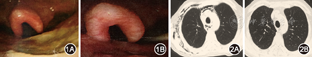

患者男,48岁。因皮肤红斑破溃伴肌无力8个月,咽痛、吞咽困难4个月于2012年2月入北京协和医院风湿免疫科。患者8个月前出现眶周、颜面、前胸、双肘关节伸侧红斑,部分破溃,伴四肢近端肌无力,上肢上举、下肢蹲起困难,伴双肩、双腕关节痛,无肿胀、晨僵;当地医院查肌酸激酶(CK)升高(不详),肌电图示肌源性损害,诊为"皮肌炎",予泼尼松40 mg/d治疗后症状好转。4个月前泼尼松减量至10 mg/d,皮疹加重,出现咽痛、声嘶并逐渐加重至吞咽困难,1个月前进展至无法进食、饮水,伴发热,体温38 ℃,咳嗽、咳少量白痰,就诊于北京协和医院急诊,行喉镜检查:鼻咽、口咽后壁、声带脓苔、白膜(图1A)。留置胃管未成功,疑有食管梗阻。为进一步诊治入院。起病后体重下降20 kg。既往、个人、婚育、家族史无特殊。入院体格检查:体温36.5℃,心率90次/min,呼吸18次/min,血压95/60 mmHg(1 mmHg=0.133 kPa);营养较差,体型偏瘦,颜面、颈部、胸前V区暗红色斑丘疹,头皮脱屑。多个手指指端溃疡、坏死,左手背及左侧肘关节可见新鲜破溃,创面较深,黄色脓苔,右肩部、右肘关节、右手多个近端指间关节、掌指关节、左臀部、双足跟及第一跖趾关节伸面多处斑丘疹、溃疡、结痂。咽后壁深大溃疡,附黄白色脓苔。颈部、右胸部皮下握雪感。双下肺闻及少量湿啰音。心、腹(–)。双下肢无水肿。双上肢近端肌力Ⅳ级,双下肢近端肌力Ⅴ–级。实验室检查:血常规:白细胞5.45×109/L,血红蛋白111 g/L,血小板143×109/L。血生化:丙氨酸转移酶59 U/L,天冬氨酸转移酶34 U/L,白蛋白22 g/L,肌酐62 μmol/L,尿素12.25 mmol/L;CK 13 U/L,乳酸脱氢酶293 U/L。超敏C反应蛋白(hsCRP)21.49 mg/L;红细胞沉降率(ESR) 77 mm/1 h;免疫球蛋白、补体、类风湿因子正常;抗核抗体、抗可提取核抗原抗体、抗磷脂抗体、肌炎抗体谱阴性。肿瘤筛查:CA125稍高,余正常。全身骨扫描、腹部CT正常。胸部CT(图2A):双肺间质病变,左肺尖肺大泡,胸膜增厚,右侧胸部皮下、纵隔气肿。心脏超声:左室顺应性减低,微量心包积液。咽部溃疡活检病理:急慢性炎,可见炎性渗出坏死及真菌菌丝。六胺银染色(+)。上消化道造影:喉咽部瘘,皮下、纵隔显影(图3),食管下段可疑狭窄。皮肤破溃处拭子培养:甲氧西林敏感金黄色葡萄球菌。

诊断皮肌炎,肺间质病变,咽部穿孔,咽喉真菌感染,皮下、纵隔气肿。予甲泼尼龙40 mg/d静脉输液治疗,静脉注射环磷酰胺(CTX)0.4 g/周治疗,同时两性霉素B、先锋美他醇等抗感染治疗。CT引导下置入空肠营养管行肠内营养支持,局部皮肤破溃伤口每日换药。经近3个月的治疗,患者体温正常,颈部、右前胸皮下握雪感消失,咽部、声带溃疡融合、变浅(图1B),声带运动恢复,皮肤红斑、破溃变浅,四肢肌力好转,复查ESR、hsCRP降至大致正常,胸部CT肺间质病变好转,皮下、纵隔气肿消失(图2B),一般情况改善,拔除空肠营养管,恢复自主饮食,激素改为泼尼松50 mg/d口服出院。出院后激素规律减量,继续使用CTX静脉注射0.4~0.6/2周,目前随诊1年余,病情稳定,泼尼松已减至5 mg/d,CTX 50 mg隔日1次口服,皮肤破溃已痊愈,肌力恢复正常。

皮肌炎患者咽痛、吞咽困难最常见的原因为颈部深层司吞咽的肌群受累[2],此时为防止呛咳诱发吸入性肺炎,常需禁食、留置胃管肠内营养支持;其次,部分皮肌炎患者可出现由血管炎导致的咽喉部黏膜糜烂、溃疡、白斑、伪膜性炎症[3],类似于咽喉部的"Gottron征" ;再次,皮肌炎常伴发恶性肿瘤,原发于咽喉部的肿瘤可引起咽痛、吞咽困难;最后,糖皮质激素和(或)免疫抑制剂治疗在维持患者免疫低下状态的同时,会使继发感染概率明显升高,咽喉部的感染也需考虑在内。该患者咽喉部检查见到深大、苔厚、丑陋的溃疡,结合患者前期治疗疗效欠佳,体重下降明显,最先需要除外的是恶性肿瘤,因此病房多次与耳鼻喉科沟通,反复在局部进行活组织病理检查、病原学培养等,但并未找到恶性肿瘤的痕迹,却获得了真菌感染的可靠证据,且抗真菌治疗有效,同时结合患者全身皮肤血管炎严重,推测可能咽喉部黏膜也是血管炎活动的受害者,最终明确患者咽痛、吞咽困难原因为咽喉部黏膜破坏的基础上,合并了侵袭性真菌感染。